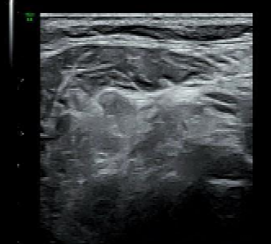

该患者外院超声检查提示甲状腺4类结节,为明确病灶性质慕名前来陆港院区就诊,经魏炜副主任超声会诊并严格评估后,明确为甲状腺左叶5类结节及双侧颈部广泛可疑淋巴结(转移?),符合甲状腺及淋巴结细针穿刺指征。在详细告知患者病情、穿刺意义和风险后,患者同意并签署知情同意书,我科尽早为患者安排了细针穿刺。在高分辨率超声实时动态引导下,穿刺针成功避开甲状腺周围重要血管、神经及气管,精准穿入目标甲状腺左叶5类结节及双侧颈部可疑淋巴结内,抽取了满意的细胞学样本。操作过程顺利,患者无明显不适及并发症,术后恢复良好。

本次穿刺获取的高质量细胞学样本满足了病理诊断需求。甲状腺细胞涂片及蜡块切片中可见“细胞异型及核沟”,提示甲状腺乳头状癌,BRAF基因V600E未检出到突变;左侧颈部III区及右侧颈部III-V区交界处淋巴结穿刺涂片及细胞蜡块切片可见“滤泡上皮细胞,细胞异型及核沟”,提示甲状腺乳头状癌转移,同时淋巴结穿刺液测得甲状腺球蛋白(Tg)>500,呈高表达,为“甲状腺乳头状癌淋巴结转移”的诊断提供了强有力的佐证。患者最终诊断明确为甲状腺乳头状癌并双侧颈部淋巴结转移,其病理结果与穿刺前超声会诊完全一致,也印证了我科在甲状腺及颈部淋巴结诊断技术能力的不断提升。